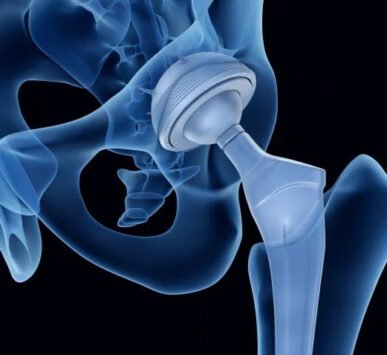

Dr. Reddy has received advanced training in arthroplasty and arthroscopy from leading medical centers in Germany, Singapore, and Australia. He is well known for his expertise in robotic joint replacement surgery, having performed more than 750 robotic-assisted procedures with excellent patient outcomes.